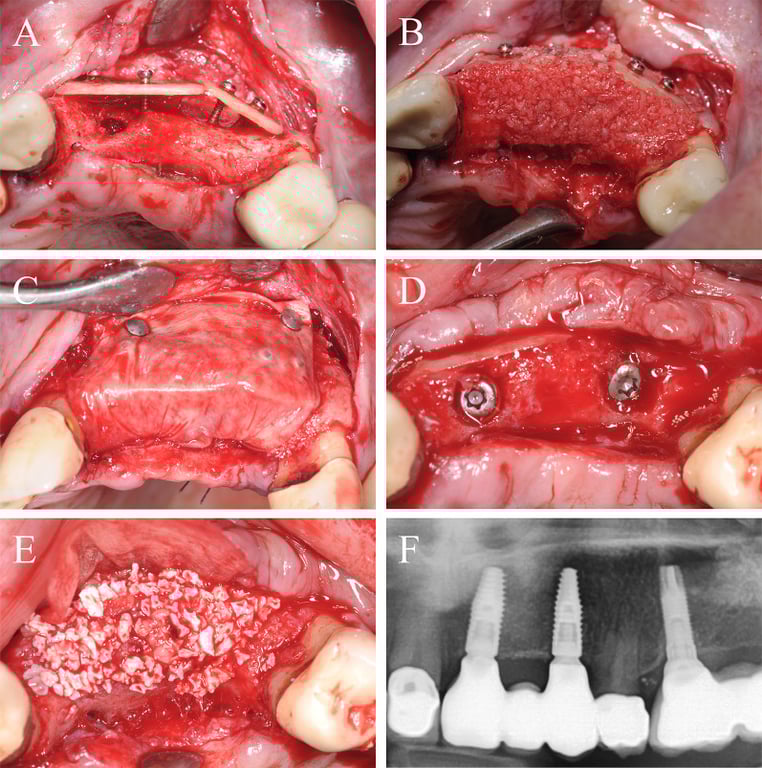

Fig. 4.

Alveolar ridge augmentation of the anterior maxilla. A Initial intraoperative situation with an extended alveolar defect of the anterior alveolar jaw. Two allogeneic cortical bone plates were fixed by fixation screws. B Intraoperative situation after filling the defect with allogeneic spongious granules. C Covering the augmented area with a porcine collagen membrane. D Implant placement 4 months later. E Overlining with xenogeneic bone graft to preserve the volume of the augmented area. F X-ray demonstrating inserted implants